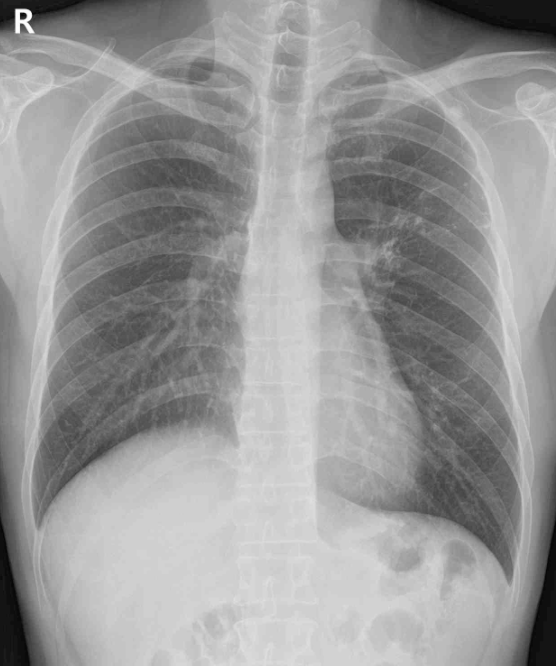

23세 남자가 1주 전부터 가슴이 아파서 병원에 왔다. 통증은 복장뼈 뒤에서 날카로운 것에 찔린 것처럼 느껴졌다. 숨을 들이마시면 심해지고 가슴을 앞으로 숙이면 완화된다고 한다. 혈압 122/70 mmHg, 맥박 78회/분, 호흡 18회/분, 체온 37.5°C이다. 혈액검사는 다음과 같다. 가슴 X선사진과 심전도이다. 진단은?

CXR: No remarkable findings

CXR: Water-bottle appearance (다량의 pericardial effusion)